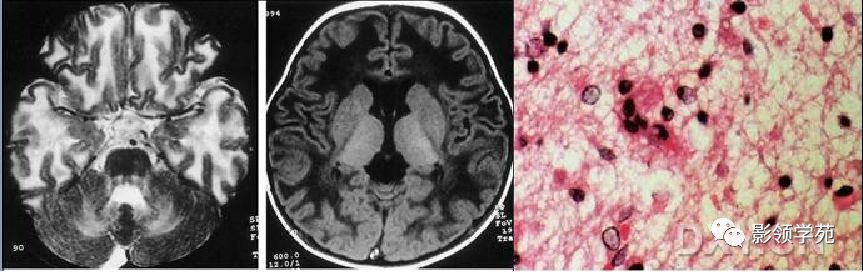

见于慢性淋巴性白血病、淋巴瘤、肾移植后、结核、结节病、系统性红斑狼疮和巨球蛋白血症等患者,发病年龄多在40岁~60岁之间 。 已证明乳多空病毒科的JC病毒和SV-40(Simian Virus猴病毒)是进行性多灶性脑白质病的病原体。 病灶多发且远离脑室周围,好发于顶枕皮质下白质内,有逐步融合增大趋势是本病较具特征性的影像学征象

麻疹病毒引起的一种罕见脑部慢性感染,多见于儿童或青少年。 表现为大脑皮层和皮层下脑白质的多发斑片状病灶,T1加权像呈低或等信号,T2加权像为高信号,增强扫描少数病例有脑膜或脑实质强化。晚期累及脑室周围白质。胼胝体、丘脑、基底节及脑干亦可受累。 本病的影像学改变无特异性。